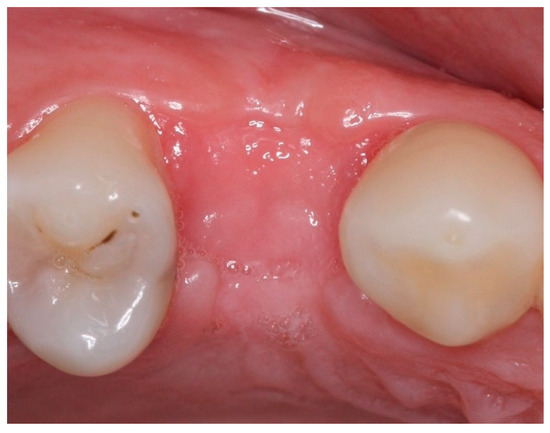

Socket Preservation Using a (Dense) PTFE Barrier with or without Xenograft Material: A Randomized Clinical Trial

2. Materials and Methods

2.4. Groups